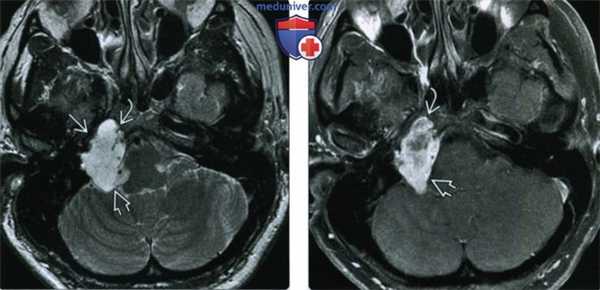

(Слева) При МРТ Т2 в аксиальной проекции определяется гиперинтенсивная правосторонняя параселлярная хондросаркома, прорастающая в предмостовую цистерну и клиновидную пазуху. Обратите внимание на смещенные опухолью внутреннюю сонную и базилярную артерию.

(Справа) При MPT Т1 FS с КУ в аксиальной проекции наблюдается умеренное контрастирование правосторонней параселлярной хондросаркомы. Пациент обратился за медицинской помощью по поводу некупируемой головной боли, носовых кровотечений и диплопии. Опухоль прорастает предмостовую цистерну и клиновидную пазуху, частично окружает правую внутреннюю сонную артерию и смещает базилярную артерию.